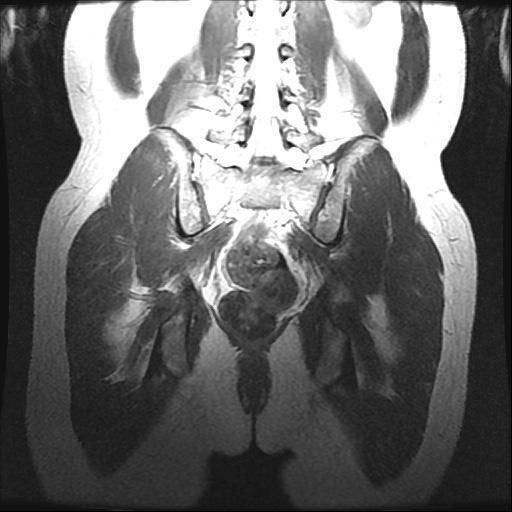

강직성척추염 의심(xray 및 mri 첨부)

인터넷 검색 후 강직성척추염을 알게 되어 말씀 드렸더니 스트레칭??을 해보시고 아닌 것 같은데 걱정이 된다고 하니 x-ray 및 mri를 찍어보자고 하셨습니다. (유전자검사는 채혈 후 대기 중)

xray 및 mri상에도 의심소견이 없다고 하셨는데

사진으로 염증이 있는지 확인 부탁드립니다.

강직성척추염과같은 염증성질환의경우 엑스레이로만은 확인하기가 어려운데요 다른 인자검사라던가 정확한 진단을위한 MRI검사등이 필요할수있습니다

올려주신 엑스레이나 MRI를 참고할 때, 또는 진료시 스트레칭을 통한 허리 및 천장관절의 유연선 평가와 개인에 따라 다르지만 대표적인 강직성 척추염의 증상이 크게 없는 것으로 보아 발생 가능성이 낮을 수 있습니다.

강직성 척추염은 주로 허리의 움직임 제한 및 영상검사에서 관절염에 해당하는 소견과, 혈액검사등에서 염증수치가 증가되어있는 경우가 많지만 이에 해당하지 않는다면 가능성은 낮다고 볼 수 있습니다.